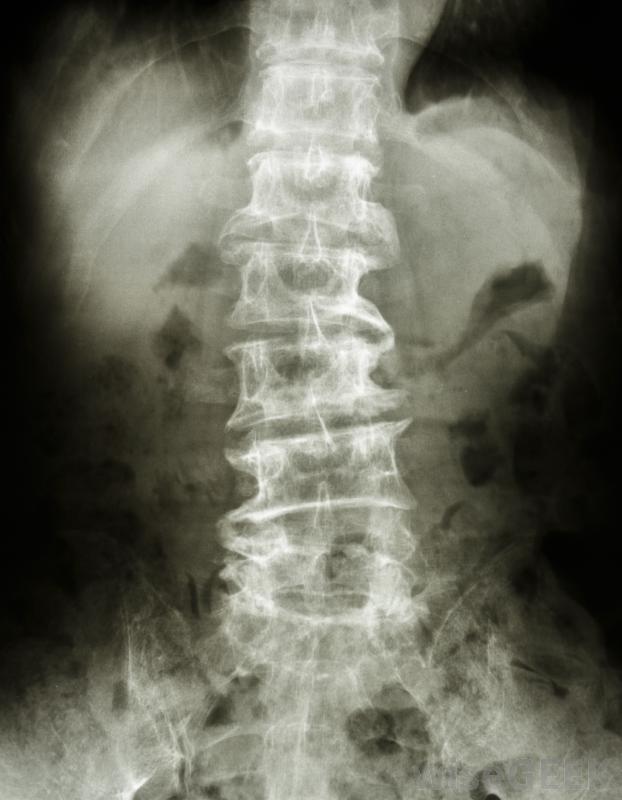

随着时间的推移,位于椎骨之间的椎间盘可能会滑出原位或退化。椎骨中也会形成骨刺,压迫敏感神经。如果椎间盘滑出原位,柔软的中央部分会压迫神经,导致腿部和背部疼痛,如果椎间盘退化,神经通过的开口会变小,导致神经受压这两个事件之间的差异是椎间盘切除术和椎板切除术之间区别的根源。

出现骨刺可能会使人的椎管变窄